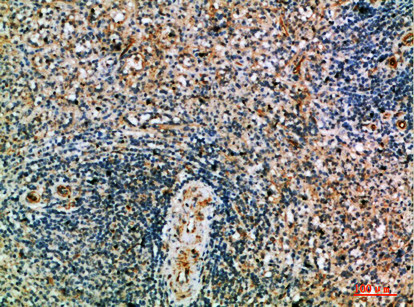

| Short Description | Rabbit polyclonal anti-Perforin-1 (451-500 aa) for use in WB, IHC and ELISA in Human, Rat and Mouse samples. Datasheet included with dilution recommendations, and related reagents. |

| Applications | WB/IHC/ELISA |

| Dilution Range | WB 1:500-2000IHC 1:50-200ELISA 1:10000-20000 |